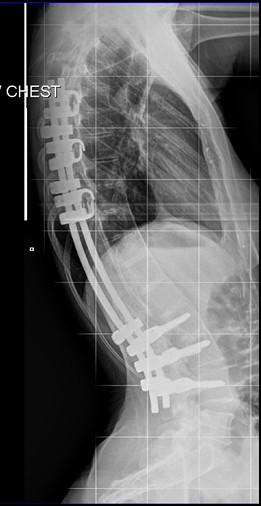

I'm Kristy. I was born with a benign spinal cord astrosytoma, a rare tumor that grew inside of my spinal cord. The doctor told my parents when they discovered the tumor that I had a better chance of winning the New York lottery than having the type of tumor in the location that I had it. I've had three tumor removal surgeries due to the tumor growing back several times and a lifetime supply of radiation treatment to kill it and prevent from growing any further. I've had 19 surgeries total, including rods inside my back, a spinal fusion for scoliosis, two leg lengthenings, and a foot reconstruction. Due to all of the surgeries and complications from the tumor, I was told I would never walk again. I've beaten the odds several times, and have learned to walk all over again starting from a wheelchair, to a walker, then to a cane and now just a full length KAFO leg brace. I am physically disabled on the left side of my body and walk with a limp.